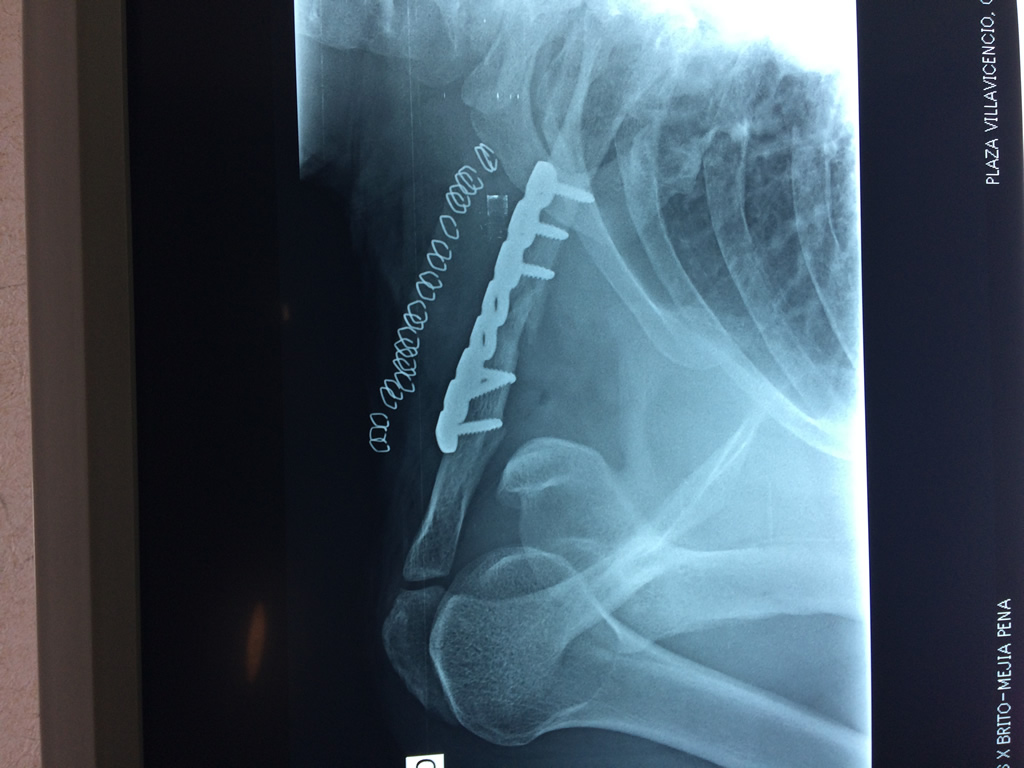

Cirugías de Húmero - Clavícula